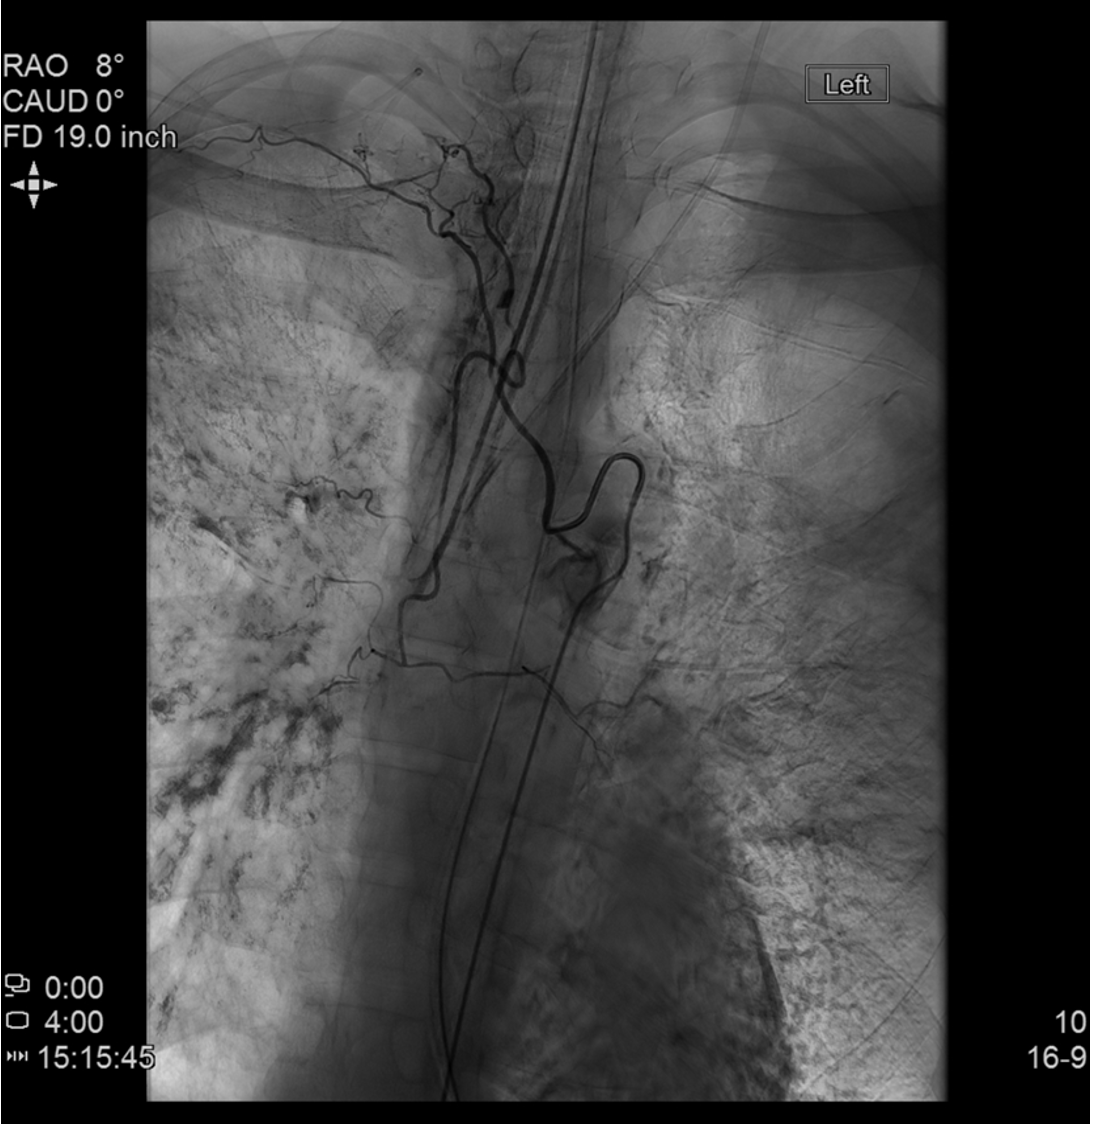

Selective intercostal angiogram showing the classic midline "hairpin" configuration of the anterior spinal artery arising from a radiculomedullary branch — mandates microcatheter superselection distal to this branch before embolization.